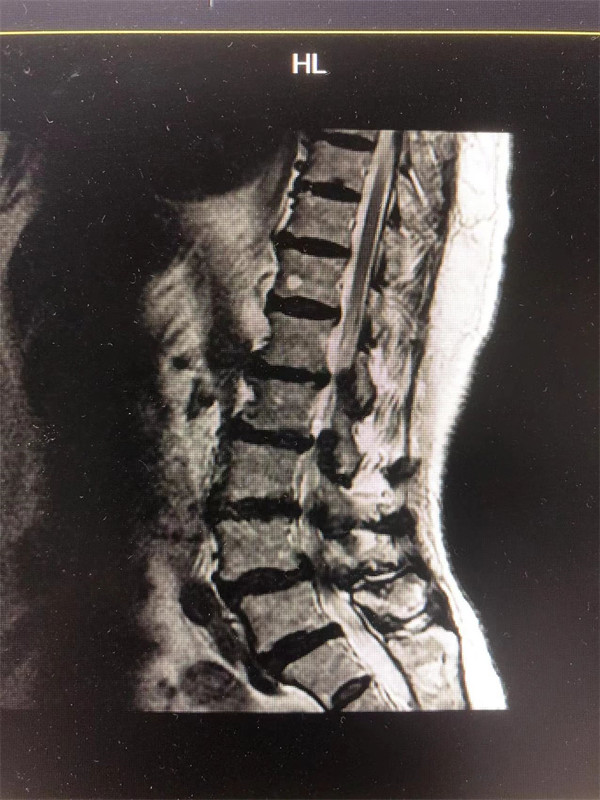

戈主任仔細詢問阿婆病情癥狀,綜合查體及MRI片情況,認為阿婆有明顯的腰椎滑脫,腰椎管狹窄,這是引發(fā)阿婆病痛的主要因素。

手術前↓